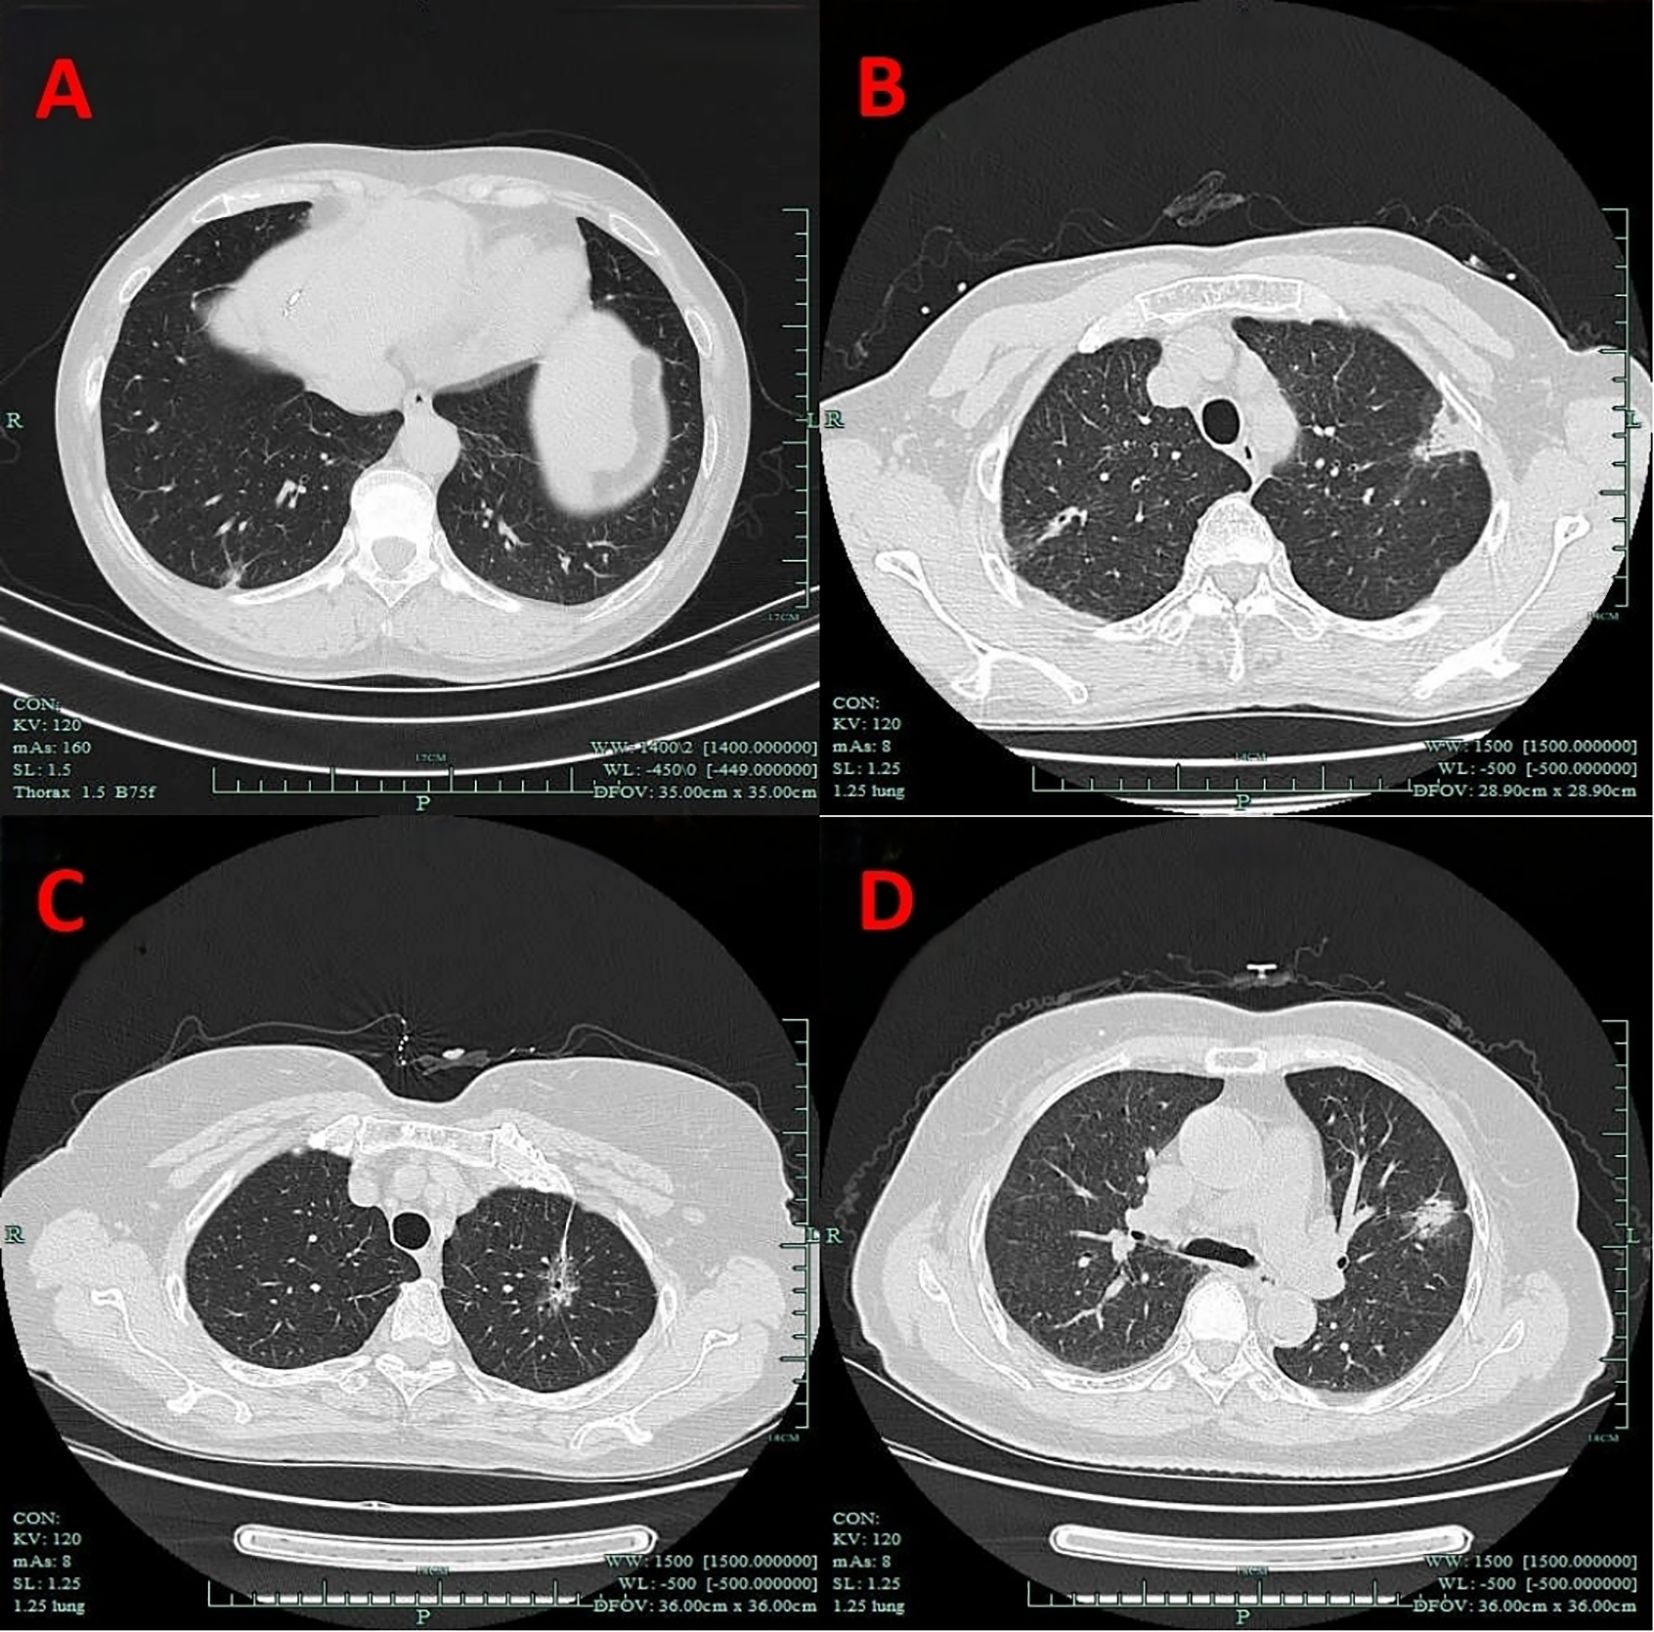

Nodule depth was defined as the distance from the pulmonary nodule to the pleura, relative to the distance from the pleura to the hilum, categorized into the outer one-third and the inner two-thirds, and it did not include centrally located lung masses (Figure 1).

Figure 1. Imaging manifestations of nodule depth. (A) The outer one-third. (B) The inner two-thirds. (C) Centrally located lung masses.

VPC represent a broad concept that includes any form of pleural involvement, such as thickening or adhesion, without penetrating the elastic layer or invading the visceral pleura (14). The key imaging manifestations of VPC include pleural traction, pleural tail sign, pleural attachment, and pleural indentation (Figure 2). In this study, VPC referred exclusively to visceral pleural involvement without visceral pleural invasion (VPI).

Figure 2. Imaging manifestations of VPC. (A) Pleural indentation. (B) Pleural attachment. (C) Pleural traction. (D) Pleural tail sign. VPC, visceral pleural changes.